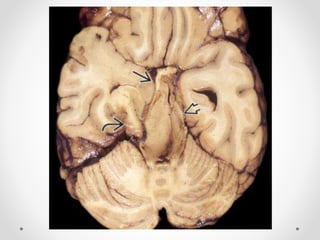

Xuất huyết Duret

- Là một hoặc nhiều ổ xuất huyết nhỏ ở cầu và hành não, sau

thoát vị qua lều hướng xuống, đặc biệt là thoát vị trung tâm.

Thường thấy ở BN có thoát vị trung tâm mức độ nặng từ 12-

24h trước khi chết

 Hình ảnh điển hình: một ổ xuất huyết tròn, nhỏ nằm ở đường

giữa hành não hoặc cầu não vị trí nối với cuống não.

 Chẩn đoán phân biệt:

- Xuất huyết do tăng huyết áp nguyên phát: thường lớn hơn,

nằm ở phần giữa cầu não, không có thoát vị não

- Dập não/ tổn thương sợi trục lan toả: ở mặt lưng của thân não(

quanh cống não và mảnh sinh tư), thường đa ổ và kích thước

nhỏ hơn